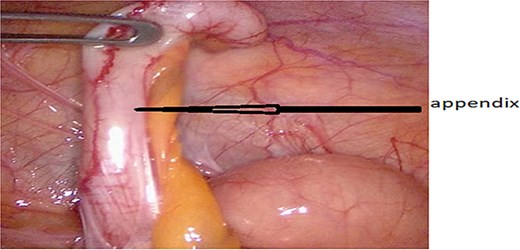

After obtaining informed consent and providing the patient with information about the case, he was transferred to the operating room after preparation, including rehydration, proton pump inhibitor (PPI), antibiotic therapy, and analgesia. Urgent exploratory laparoscopy confirmed the CT findings: retrocecal appendicitis with minimal peritoneal effusion (Fig. 3) in the Douglas pouch. A careful dissection of the appendix from its mesentery was performed, followed by appendectomy (Fig. 4), lavage, and drainage.